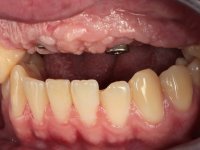

O paciente foi observado conjuntamente e a dúvida que surgiu de imediato foi se seria possível com a regeneração óssea a efectuar poder ser reabilitada naturalmente a zona das papilas interdentárias. Nesse sentido foi feito um enceramento de diagnóstico que contemplaria as duas hipóteses, utilizando ou não a cerâmica gengival. A confecção desse enceramento foi fundamental para expor ao paciente a dificuldade da reabilitação. O wax-up deu origem a um mock-up que foi aprovado pelo paciente e que simultaneamente serviu de guia imagiológica. O caso foi planificado cirurgicamente e realizada uma guia cirúrgica com que foram colocados os implantes. Após 10 semanas foi feita a 1ª impressão para confecção da ponte provisória. Foram criados os primeiros perfis de emergência na gengiva artificial e foi digitalizado o modelo. Por processo de CAD-CAM foi confeccionada uma ponte provisória aparafusada baseada no enceramento de diagnóstico. A ponte trabalhou durante 8 semanas os tecidos moles que foram fielmente copiados numa impressão com técnica de moldeira aberta. Os transferes foram individualizados com resina composta para copiarem fielmente os perfis de emergência criados pela ponte provisória. Confeccionado o modelo de trabalho definitivo, foi realizada uma infra-estrutura em zircónio seguindo a orientação do enceramento de diagnóstico. O assentamento da infra-estrutura foi testado em boca e simultaneamente foi novamente impressionados os tecidos moles com um silicone fluido. Nessa consulta foi feito o levantamento da cor. Os dentes 13 e 23 apresentavam uma saturação anormalmente forte que resolvemos não valorizar, optando por privilegiar a relação com o sector antero-inferior. Foi realizada uma nova gengiva artificial com a impressão que acompanhou a impressão de arrasto com a infra-estrutura. Após a colocação da cerâmica na infra-estrutura foram coladas as meso-estruturas. O trabalho final foi aparafusado lentamente permitindo a adaptação dos tecidos moles.